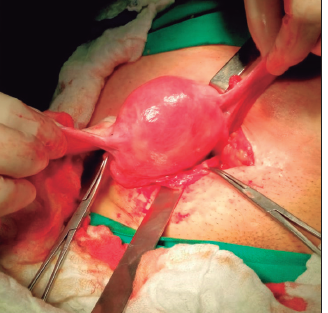

Alfonso Muñoz R., Edgard Riquelme M., Victor Sanhueza O., Daniel Reyes C.

|

|

|